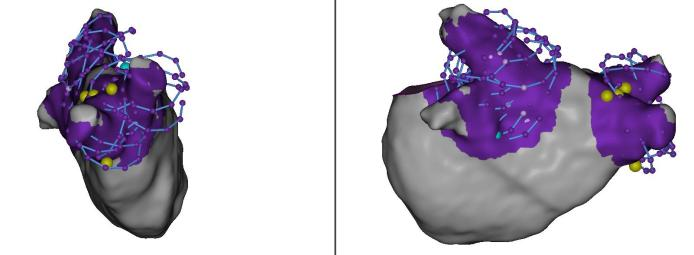

三维评判损伤形成区域:FAM coloring实时消融损伤显示,Grid overlap indication同步显示TPI阳性grid点。

规范化的手术流程以及每个环节的标准操作是保障手术效果的关键,让更多电生理医生从靠经验判断消融到可直视和可量化,看到消融的范围和效果,才是保障手术的安全性、有效性、效率的关键。